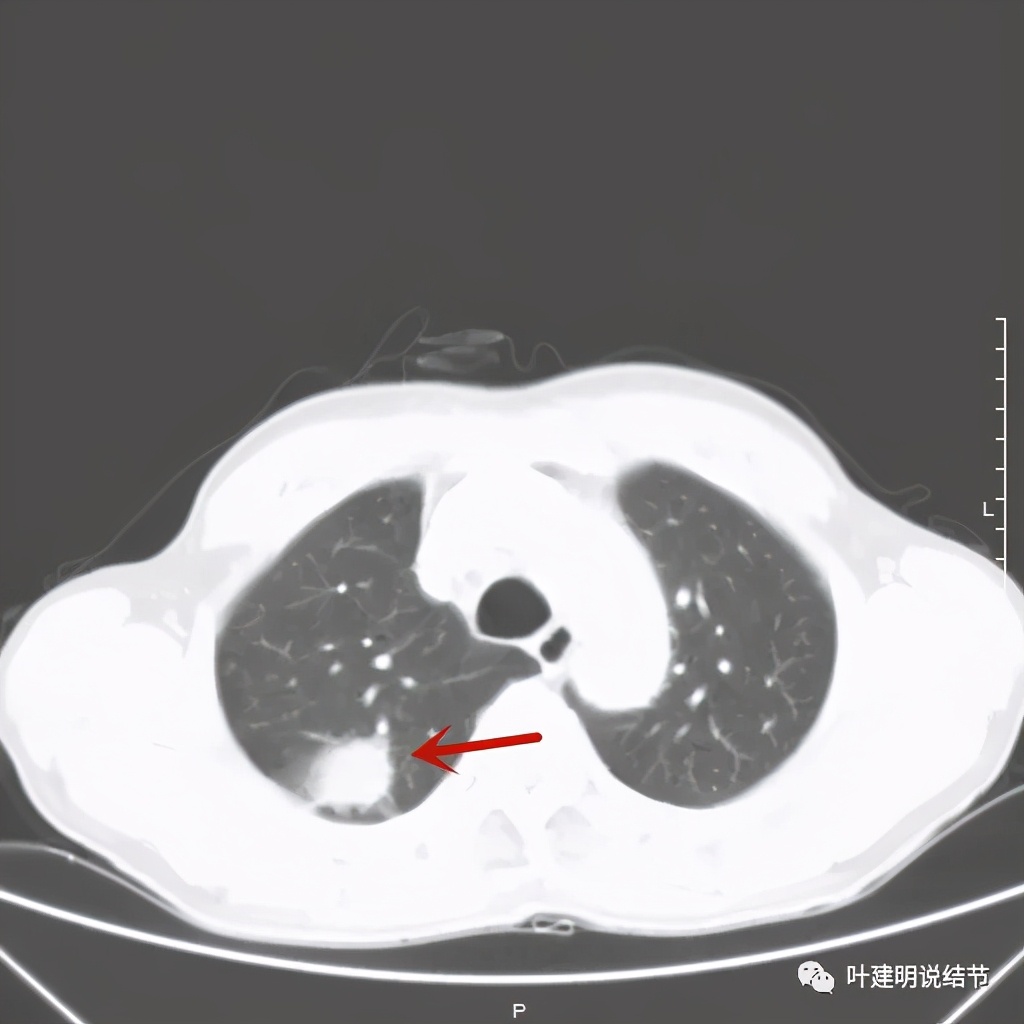

金华的某A,今年66岁,前几天在当地医院查胸部CT平扫发现右上肺占位,当时来找我看时,我想首先肺内占位是要警惕肺癌的,建议其住院进一步做增强CT,以及完善其他相关检查。其中增强CT报告示:右上叶约7*6厘米的肿块,增强后显著强化。而且某A曾于2018年5月在本院做过肺部CT,当时右上肺没有病灶的。我们先来看这次的CT图像:

红色示病灶,绿色示病灶旁边有磨玻璃成分,但较为模糊;蓝色箭头示病灶与胸膜间有牵拉,但力度不太够。

总体上感觉,病灶比较大,不规则,不是圆形或圆形生长,周围有模糊磨玻璃影(考虑炎性渗出性?),虽有胸膜牵拉,但力度不够;增强有显著强化。病灶明显却无明显临床症状,普通感染是不像的,要么是结核,要么是肺癌。但肺癌的话,在2年前没有,2年内长到这么大,恶性程度应该很高,但其纵隔淋巴结却没有明显肿大。而且病灶的边缘部分过于光滑,没有见到肿瘤的细毛刺,膨胀性也不够。整体看病灶有点像“腰子”形,弯弯曲曲的。所以我的感觉更倾向结核性。查了肿瘤筛查指标如下: